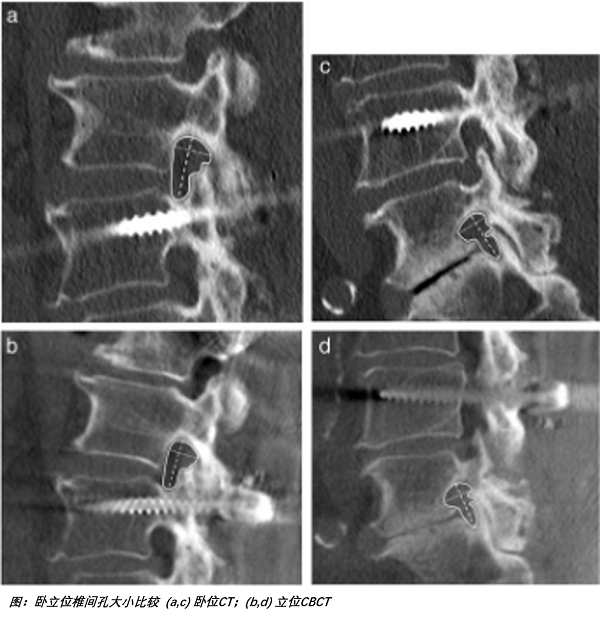

由于人体骨骼在承重与非承重状态下所承受的压力不同,关节间隙的差异在站卧之间可达数倍。CBCT平板和球管围绕患者进行等中心旋转,可实现任意体位的锥形束CT扫描,在脊柱、关节、骨骼获取传统CT检查无法企及的承重位三维图像,真实反映骨骼受力情况并找到病症根源。它引领了立位3D检查的最新方向,精确地对关节力线进行评估,是外科手术成功与远期效果评估的重要因素。